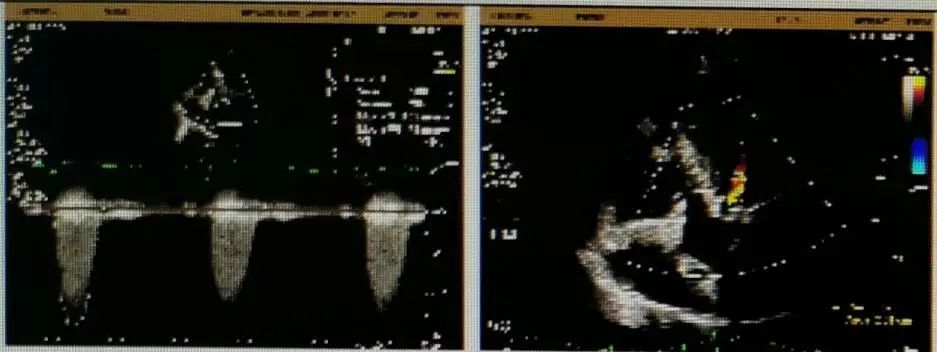

超声检查

超声结果显示主动脉瓣退行性病变,重度狭窄并轻度反流;主动脉瓣瓣口流速5.9m/s,峰值跨瓣压差138mmHg,平均跨瓣压差72mmHg,瓣环内径20mm,升主增宽,主动脉弓内径36mm,反流彩束面积2.3cm²,LVOT-VTI:28.9cm。此外,患者同时合并左室壁增厚,左室舒张功能减退,节段性室壁运动异常,重度二尖瓣反流,重度三尖瓣返流,轻度肺高压。

术后即刻跨瓣压差

主动脉根部TEE评估

对本例手术,罗建方教授团队通过术前详尽的检查分析评估,对可能发生的各种突发情况进行充分预估,并准备了相应的应对预案,手术中采用左右重叠体位,标准位释放,术后跨瓣压差降至0mmHg,血流动力学得到有效改善,为患者带来更长久的生存预期和更高的生活质量。本例手术的成功开展再次展现了罗建方教授团队在诊治高难度复杂主动脉瓣膜疾病的雄厚实力和丰富经验,也为临床上心室腔小、心肌肥厚、横位心的Type1型二叶瓣患者行TAVR治疗提供了更多的参考。